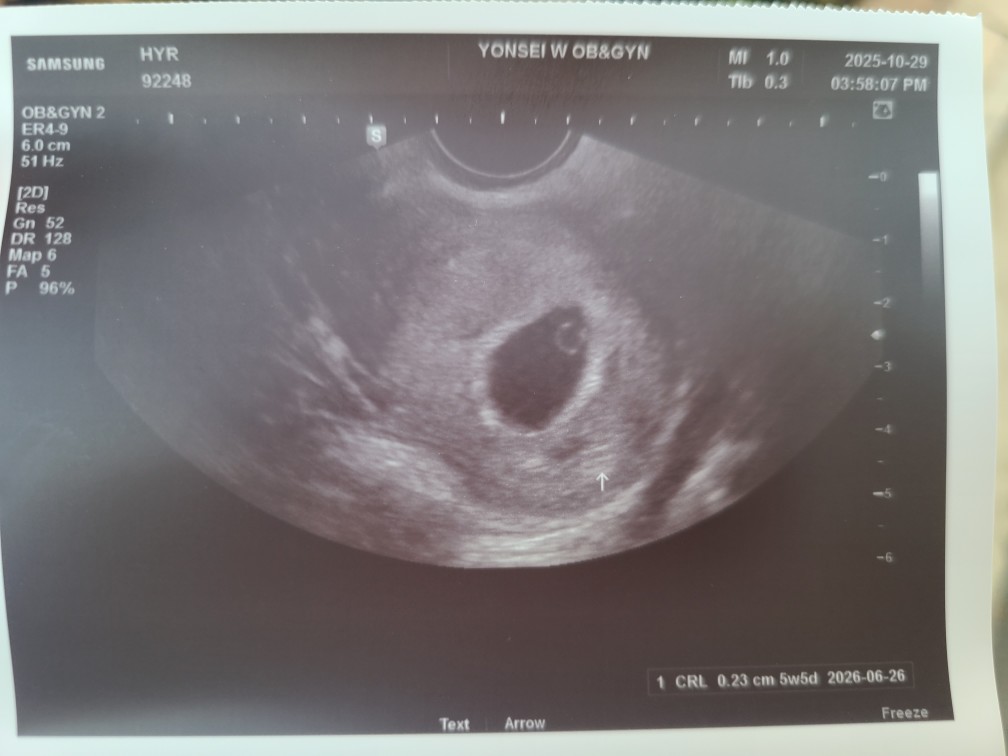

늦은 나이에 결혼하고 3년만에 가진 아이입니다. 마지막으로 자연임신 계획하고 다음부터 시험관을 생각했는데 정...